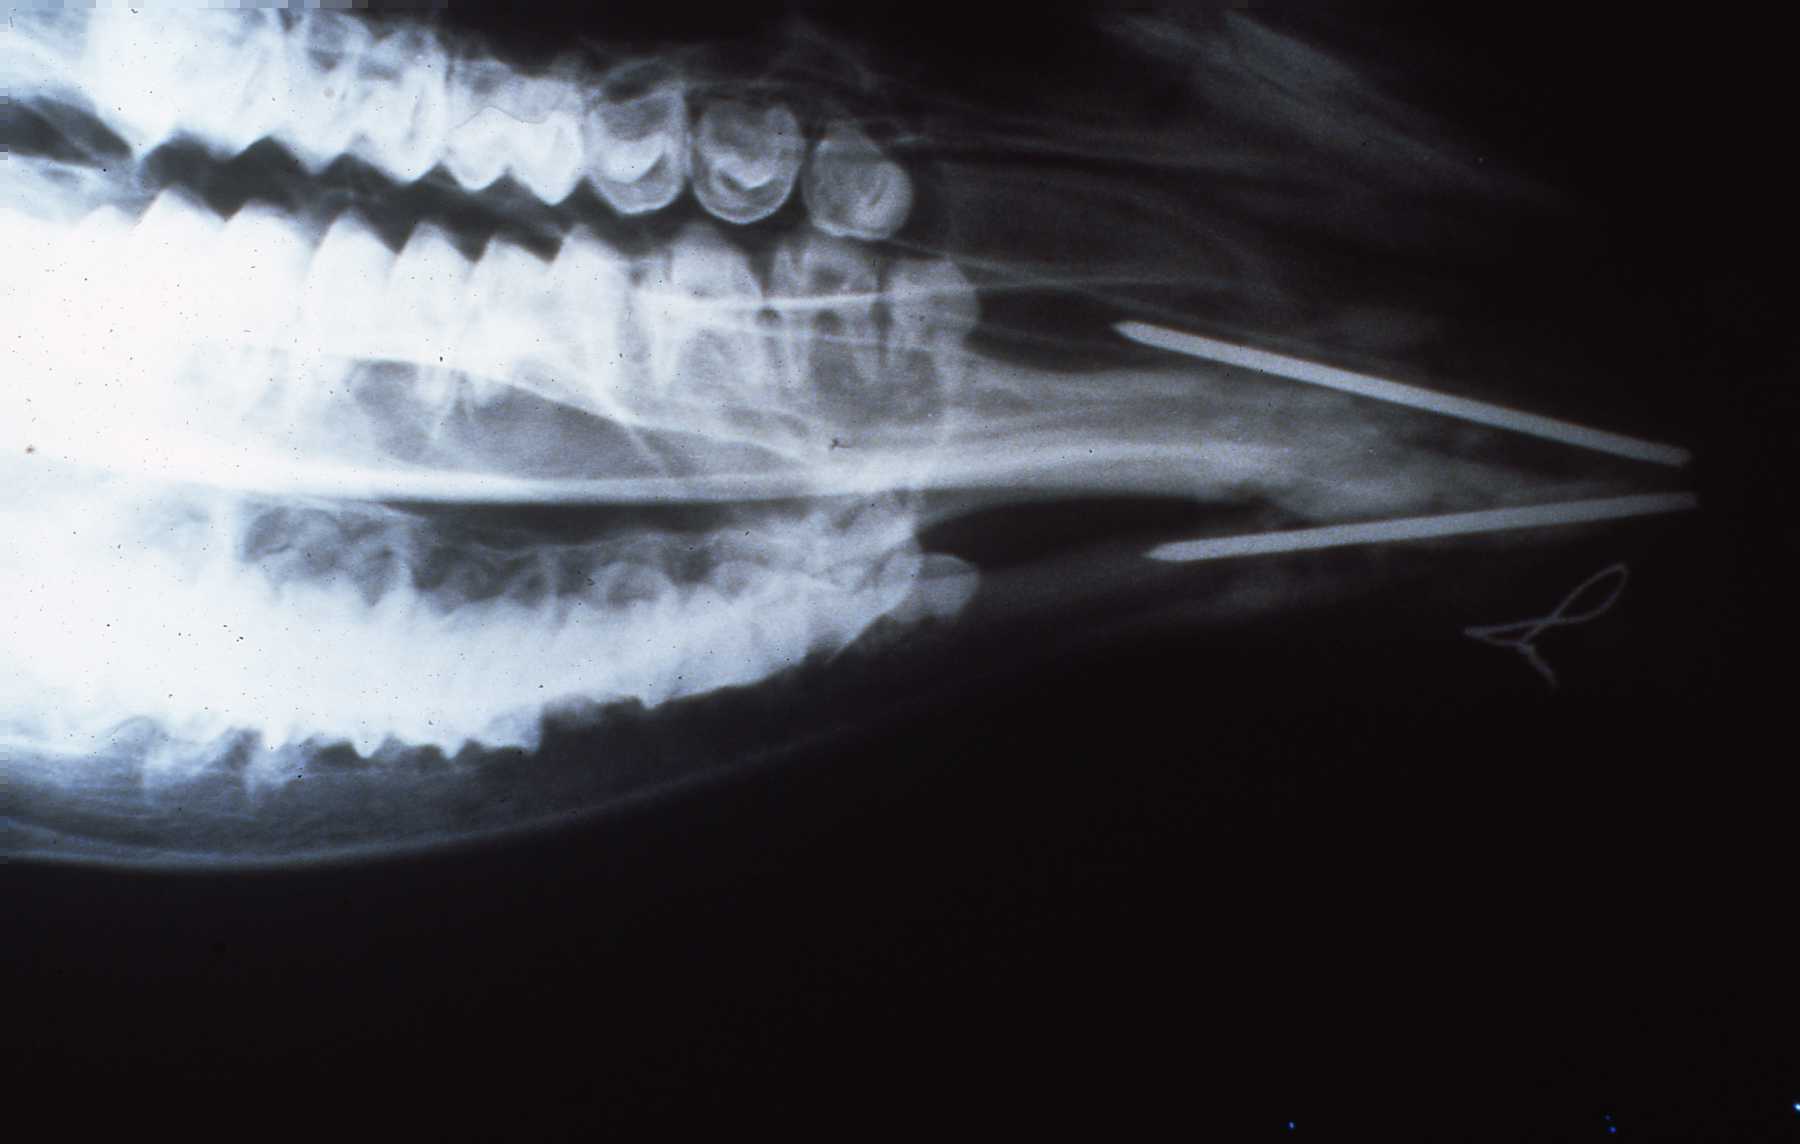

Bongo “Ira” mandible symphysis fracture presentation.

Bongo “Ira” Radiograph of remaining pins 6 months post-op.